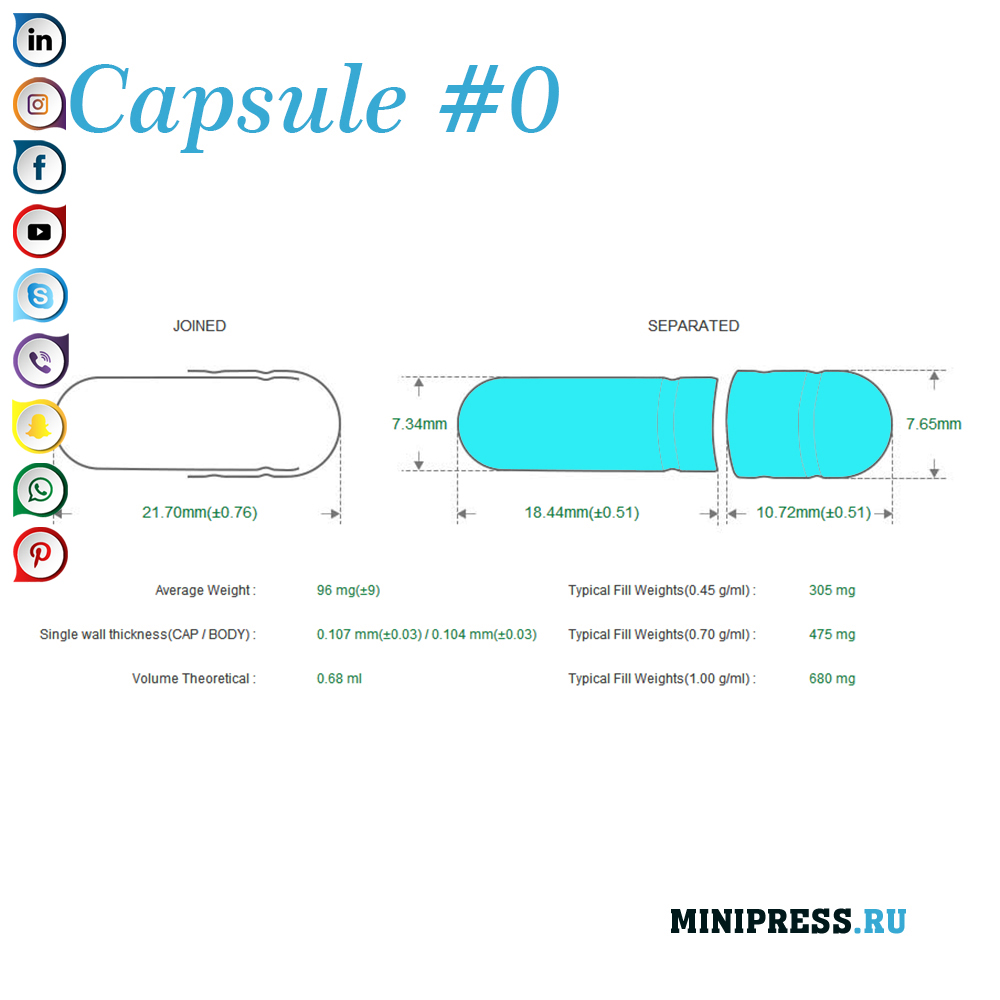

Velike zelatinskih kapsula: 000,00,0,1,2,3,4,5, A, B, C, D, E.